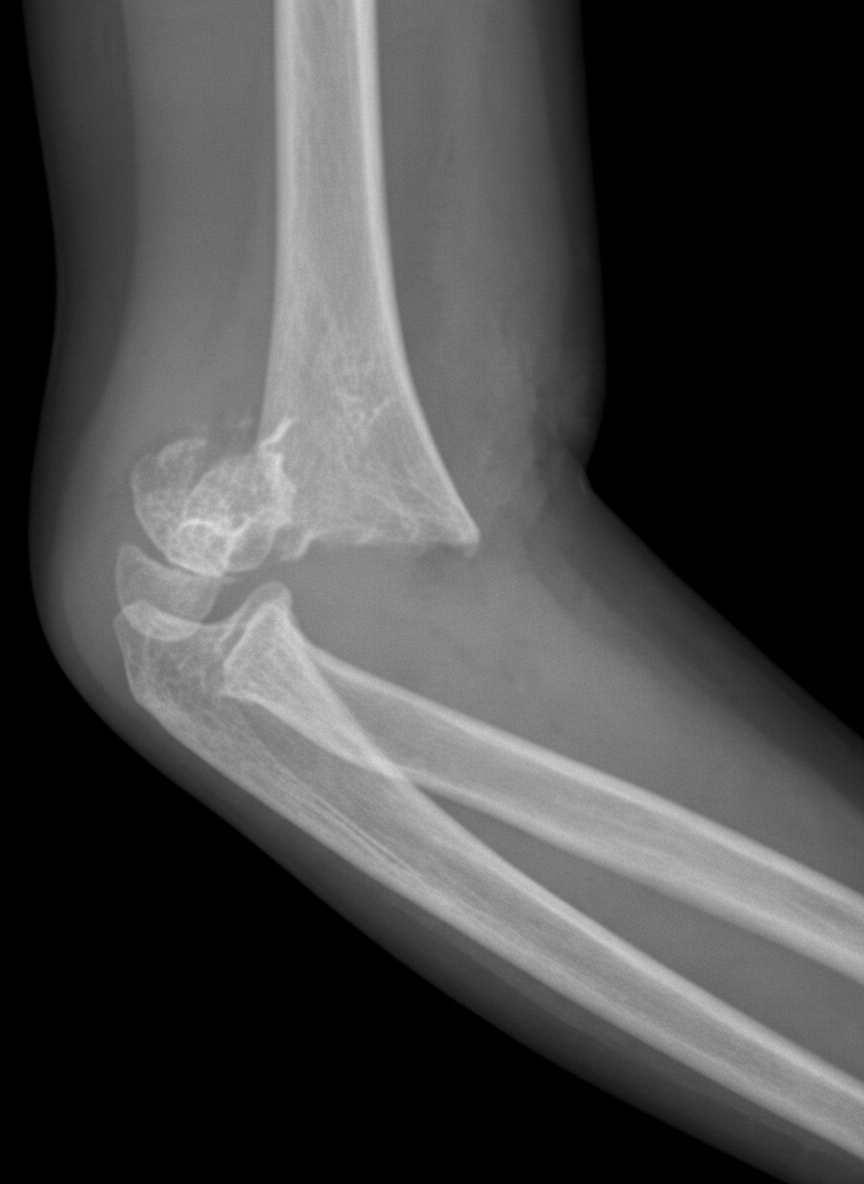

A 5-year-old boy is brought to the emergency department for right elbow swelling and pain 45 minutes after he fell while playing on the monkey bars during recess. He has been unable to move his right elbow since the fall. Examination shows ecchymosis, swelling, and tenderness of the right elbow; range of motion is limited by pain. The remainder of the examination shows no abnormalities. An x-ray of the right arm is shown. Which of the following is the most likely complication of this patient's injury?